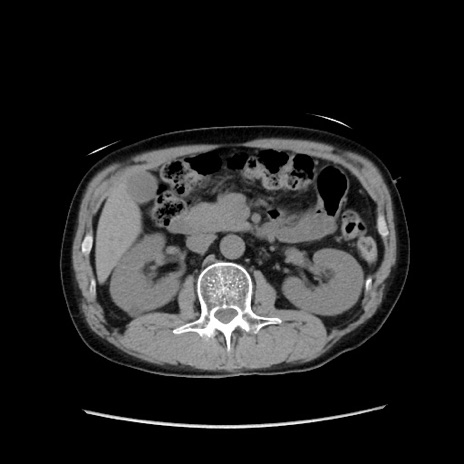

症例37(横断像)

【症例】40歳代 男性

【主訴】腹痛

【現病歴】4時間ほど前に電車に乗車中に臍部上より腹痛出現。徐々に増悪し起立困難となり、救急外来受診。生ものは数日食べていない。今朝お雑煮を食べた。

【身体所見】BT 36.8℃、BP 117/84mmHg、HR 91/min、SpO2 97%、苦悶様、腹部:臍上部広範囲圧痛あり、反跳痛±

【データ】WBC 8100、CRP 0.03